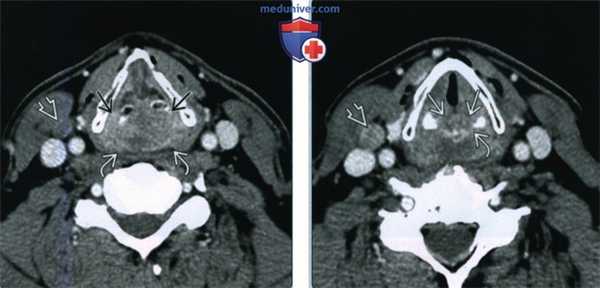

(Слева) При аксиальной КТ с КУ у курящего мужчины 55 лет, долгое время употребляющего алкоголь, у которого было обнаружено пальпируемое объемное образование шеи справа, возле бифуркации правой общей сонной артерии визуализируется увеличенный и некротически измененный лимфоузел II уровня. Была выполнена аспирационная биопсия, подтвердился ПКР. Тем не менее, первичную опухоль при клиническом обследовании выявить не удалось.

(Справа) При аксиальной КТ с КУ у этого же пациента в верхушке правого грушевидного синуса визуализируется небольшой, плохо различимый участок асимметричного накопления контраста, который был верифицирован как первичный ПКР. Обратите внимание на вторично измененный контрлатеральный лимфоузел с признаками некроза.